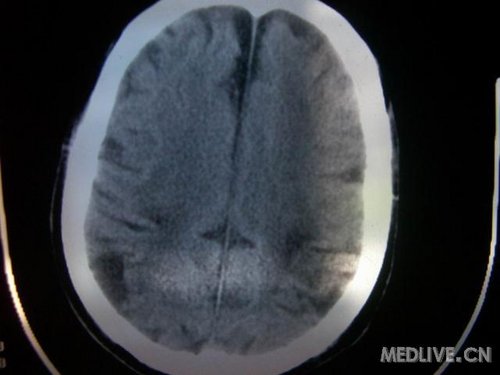

病人男性 73岁 市民 以“幻听、幻视两天,言语含糊、精神错乱一天”入院。

两天前无诱因出现幻听、幻视,描素眼前有彩色的圆圈,听见有人说话(但说什么不详),一天前出现胡言乱语,言语含糊,精神错乱,问话不答,行走略有不稳,来我院就诊,门诊头CT检查:(下面有片)入院后查体不合作,表情淡漠,问话不答,大致检查了一下,颅神经未见明显异常,颈软,右手活动似忽略差。其他检查不配合。脑电图:广泛轻-中度异常。

既往史:半年前曾患“右侧脑梗塞”但无明显后遗症,生活能自理,无高血压、糖尿病、心脏病史。

此次入院时的片子: